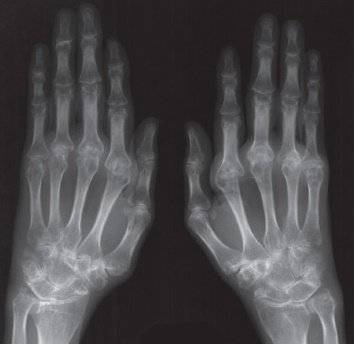

Первыми страдают мелкие суставы кистей рук, стоп. Рентгенологические признаки первой стадии ревматоидного артрита:

- преимущественное воспаление мягкотканого компонента, имеющее вид уплотнений структур над поражённым суставом;

- незначительное сужение межсуставной щели, которое не визуализируется на рентгеновском снимке;

- начальные проявления остеопороза в виде локальных просветлений костных структур и разрыхления только суставных поверхностей.